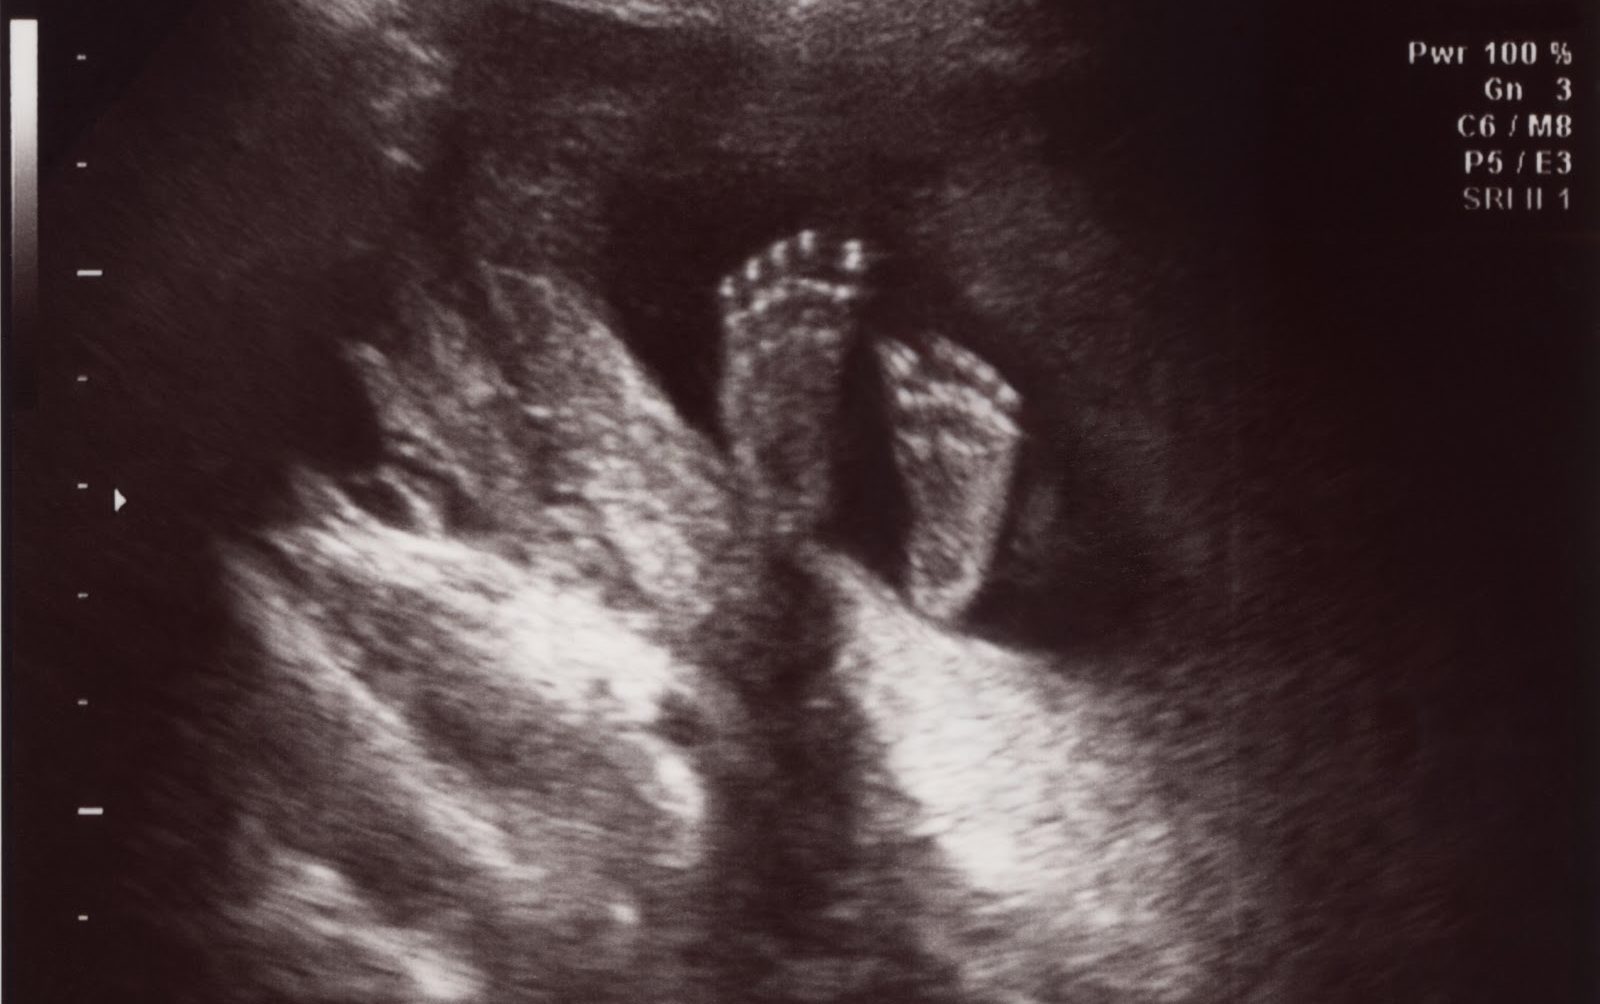

feturs-in-uero.jpg